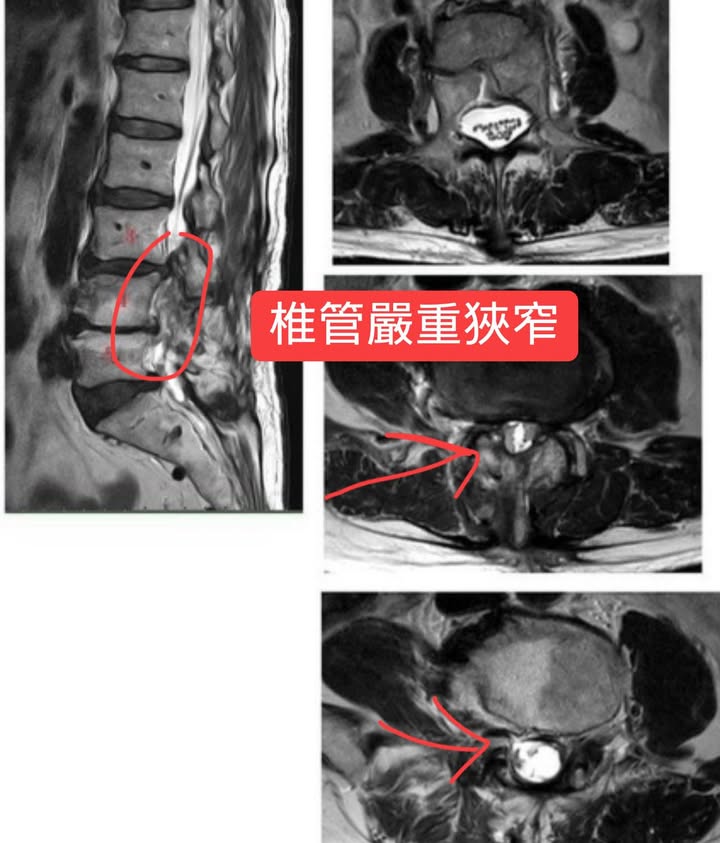

1.術後再度L3L4第三度嚴重 椎孔狹窄;L4L5;L5S1輕微 椎孔狹窄

2.腰椎核心肌群萎縮

3.術後韌帶、肌肉沾黏

4.梨狀肌症候群